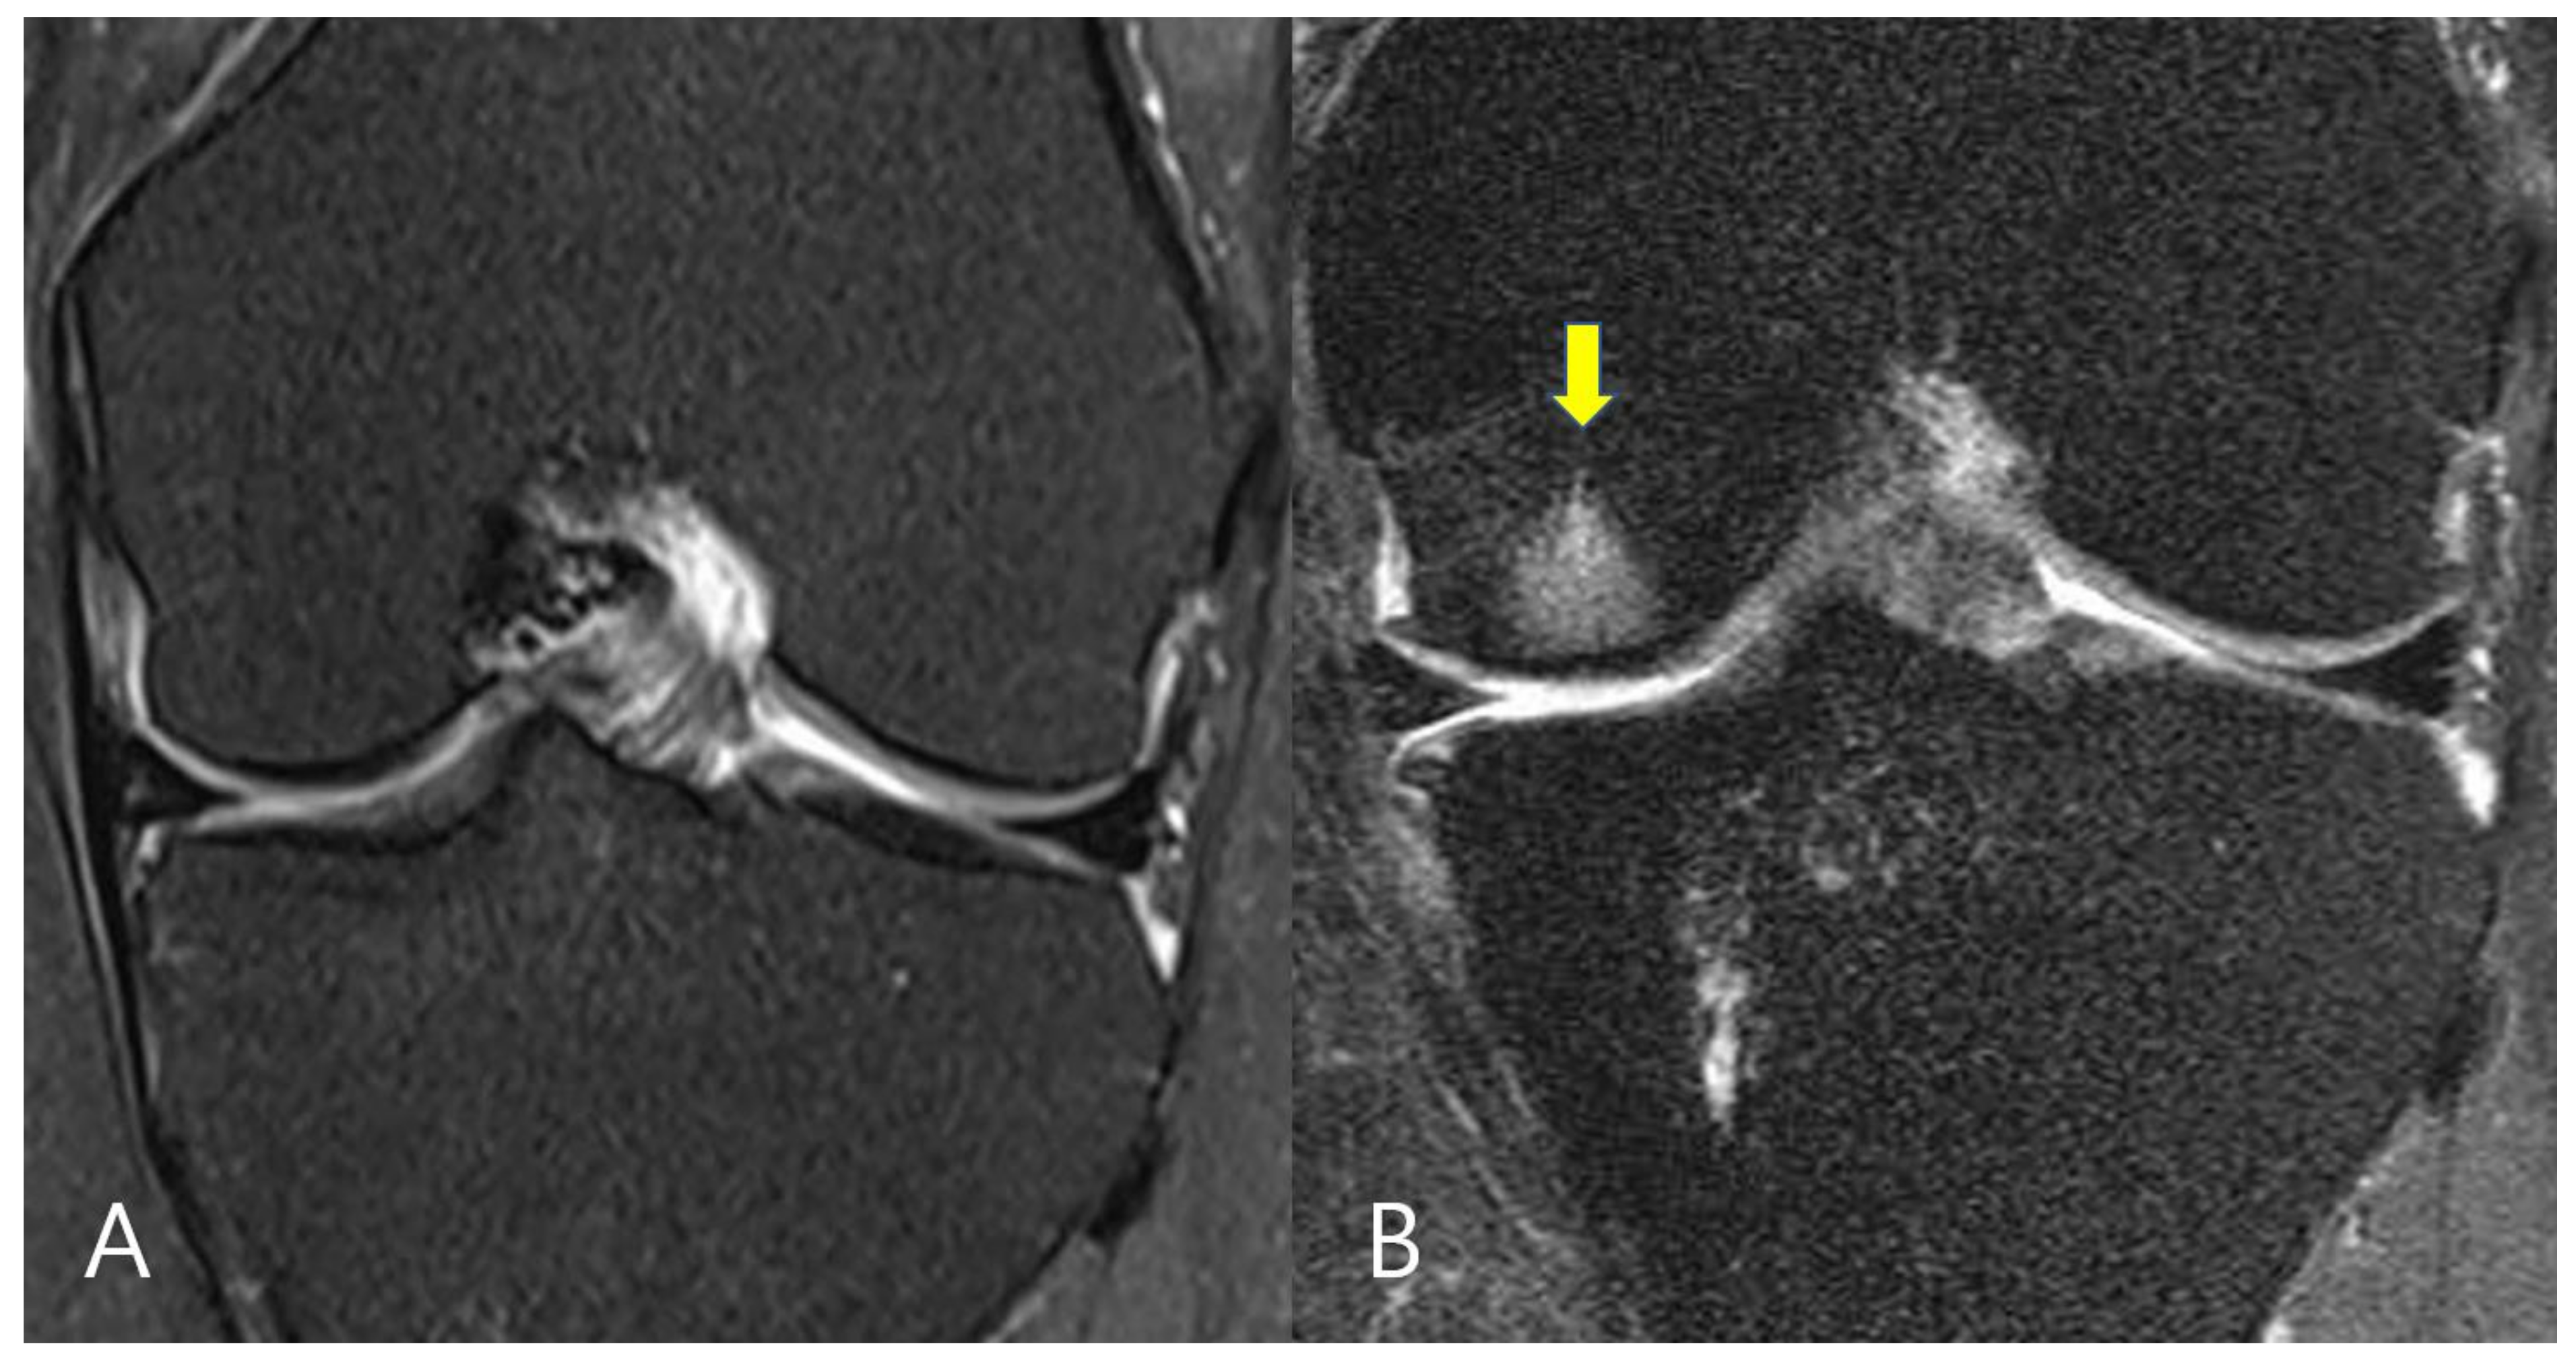

2.2. Evaluation of Bone Marrow Lesions